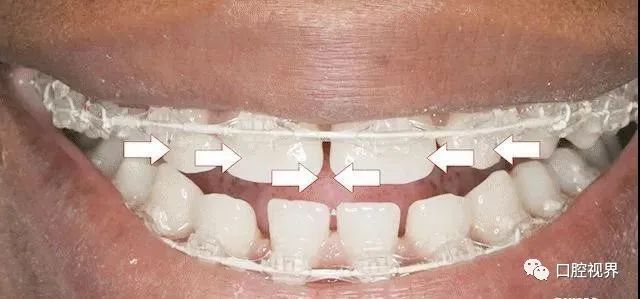

如何解决牙缝大的问题?

早些年,大多都推荐使用牙套,简单快捷,唯一的缺点就是价格稍稍贵点,量力而行吧各位!

此外,贴面修复、烤瓷牙等方法等都可以缓解牙缝过大的问题。(再次强调,不推荐全瓷牙修复,因为那样会损失大量真实牙体,当卸下牙冠你会发现牙缝好像更大了……)